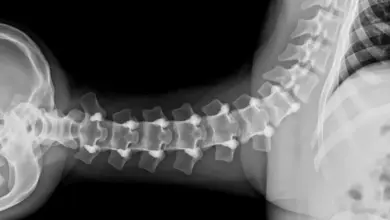

A espondilolistese displásica é um escorregamento congênito entre as vértebras, mais comum em L5 S1.

Essa variação surge por malformações das facetas e do arco posterior, o que favorece instabilidade, dor e, em alguns casos, sinais neurológicos.

É um tipo de listese de origem congênita. As facetas articulares nascem orientadas de forma anômala, o arco posterior pode comprimir a cauda equina e a translação entre L5 e S1 tende a ocorrer ao longo do crescimento.

Diferente da forma ístmica, não há obrigatoriamente fratura da pars, o problema está na anatomia que permite o deslizamento.